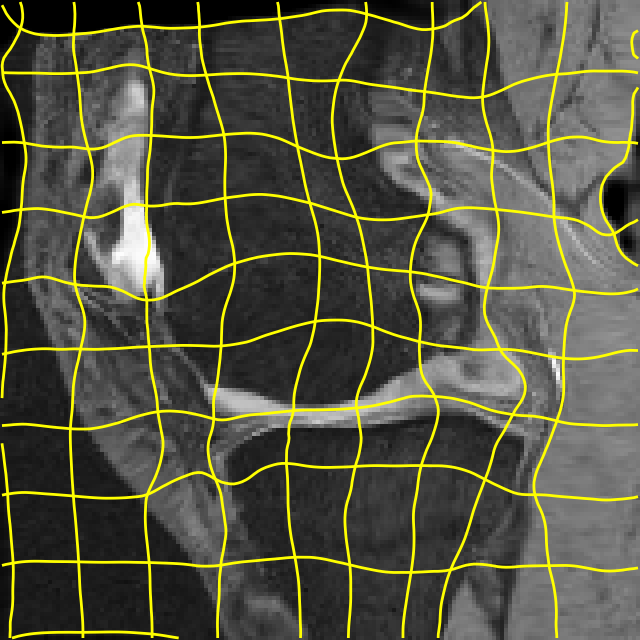

Moving

Target

Mono-0

Mono-5

DA-1

DA-5

Mono-200

Results: All trained networks are evaluated using Dice overlap scores between predictions and the manual segmentations for the segmentation network, or between the warped moving segmentations and the target segmentations for the registration network. Tabs. 1 and 2 show results for the knee and brain MRI experiments respectively in Dice scores (%). Fig. 2 shows examples of knee MRI registrations and brain MRI segmentations.

Qualitative results: DA achieves more anatomically consistent registrations than the mono-networks on the knee (Fig. 2) and Brain MRI samples (see supplementary material).